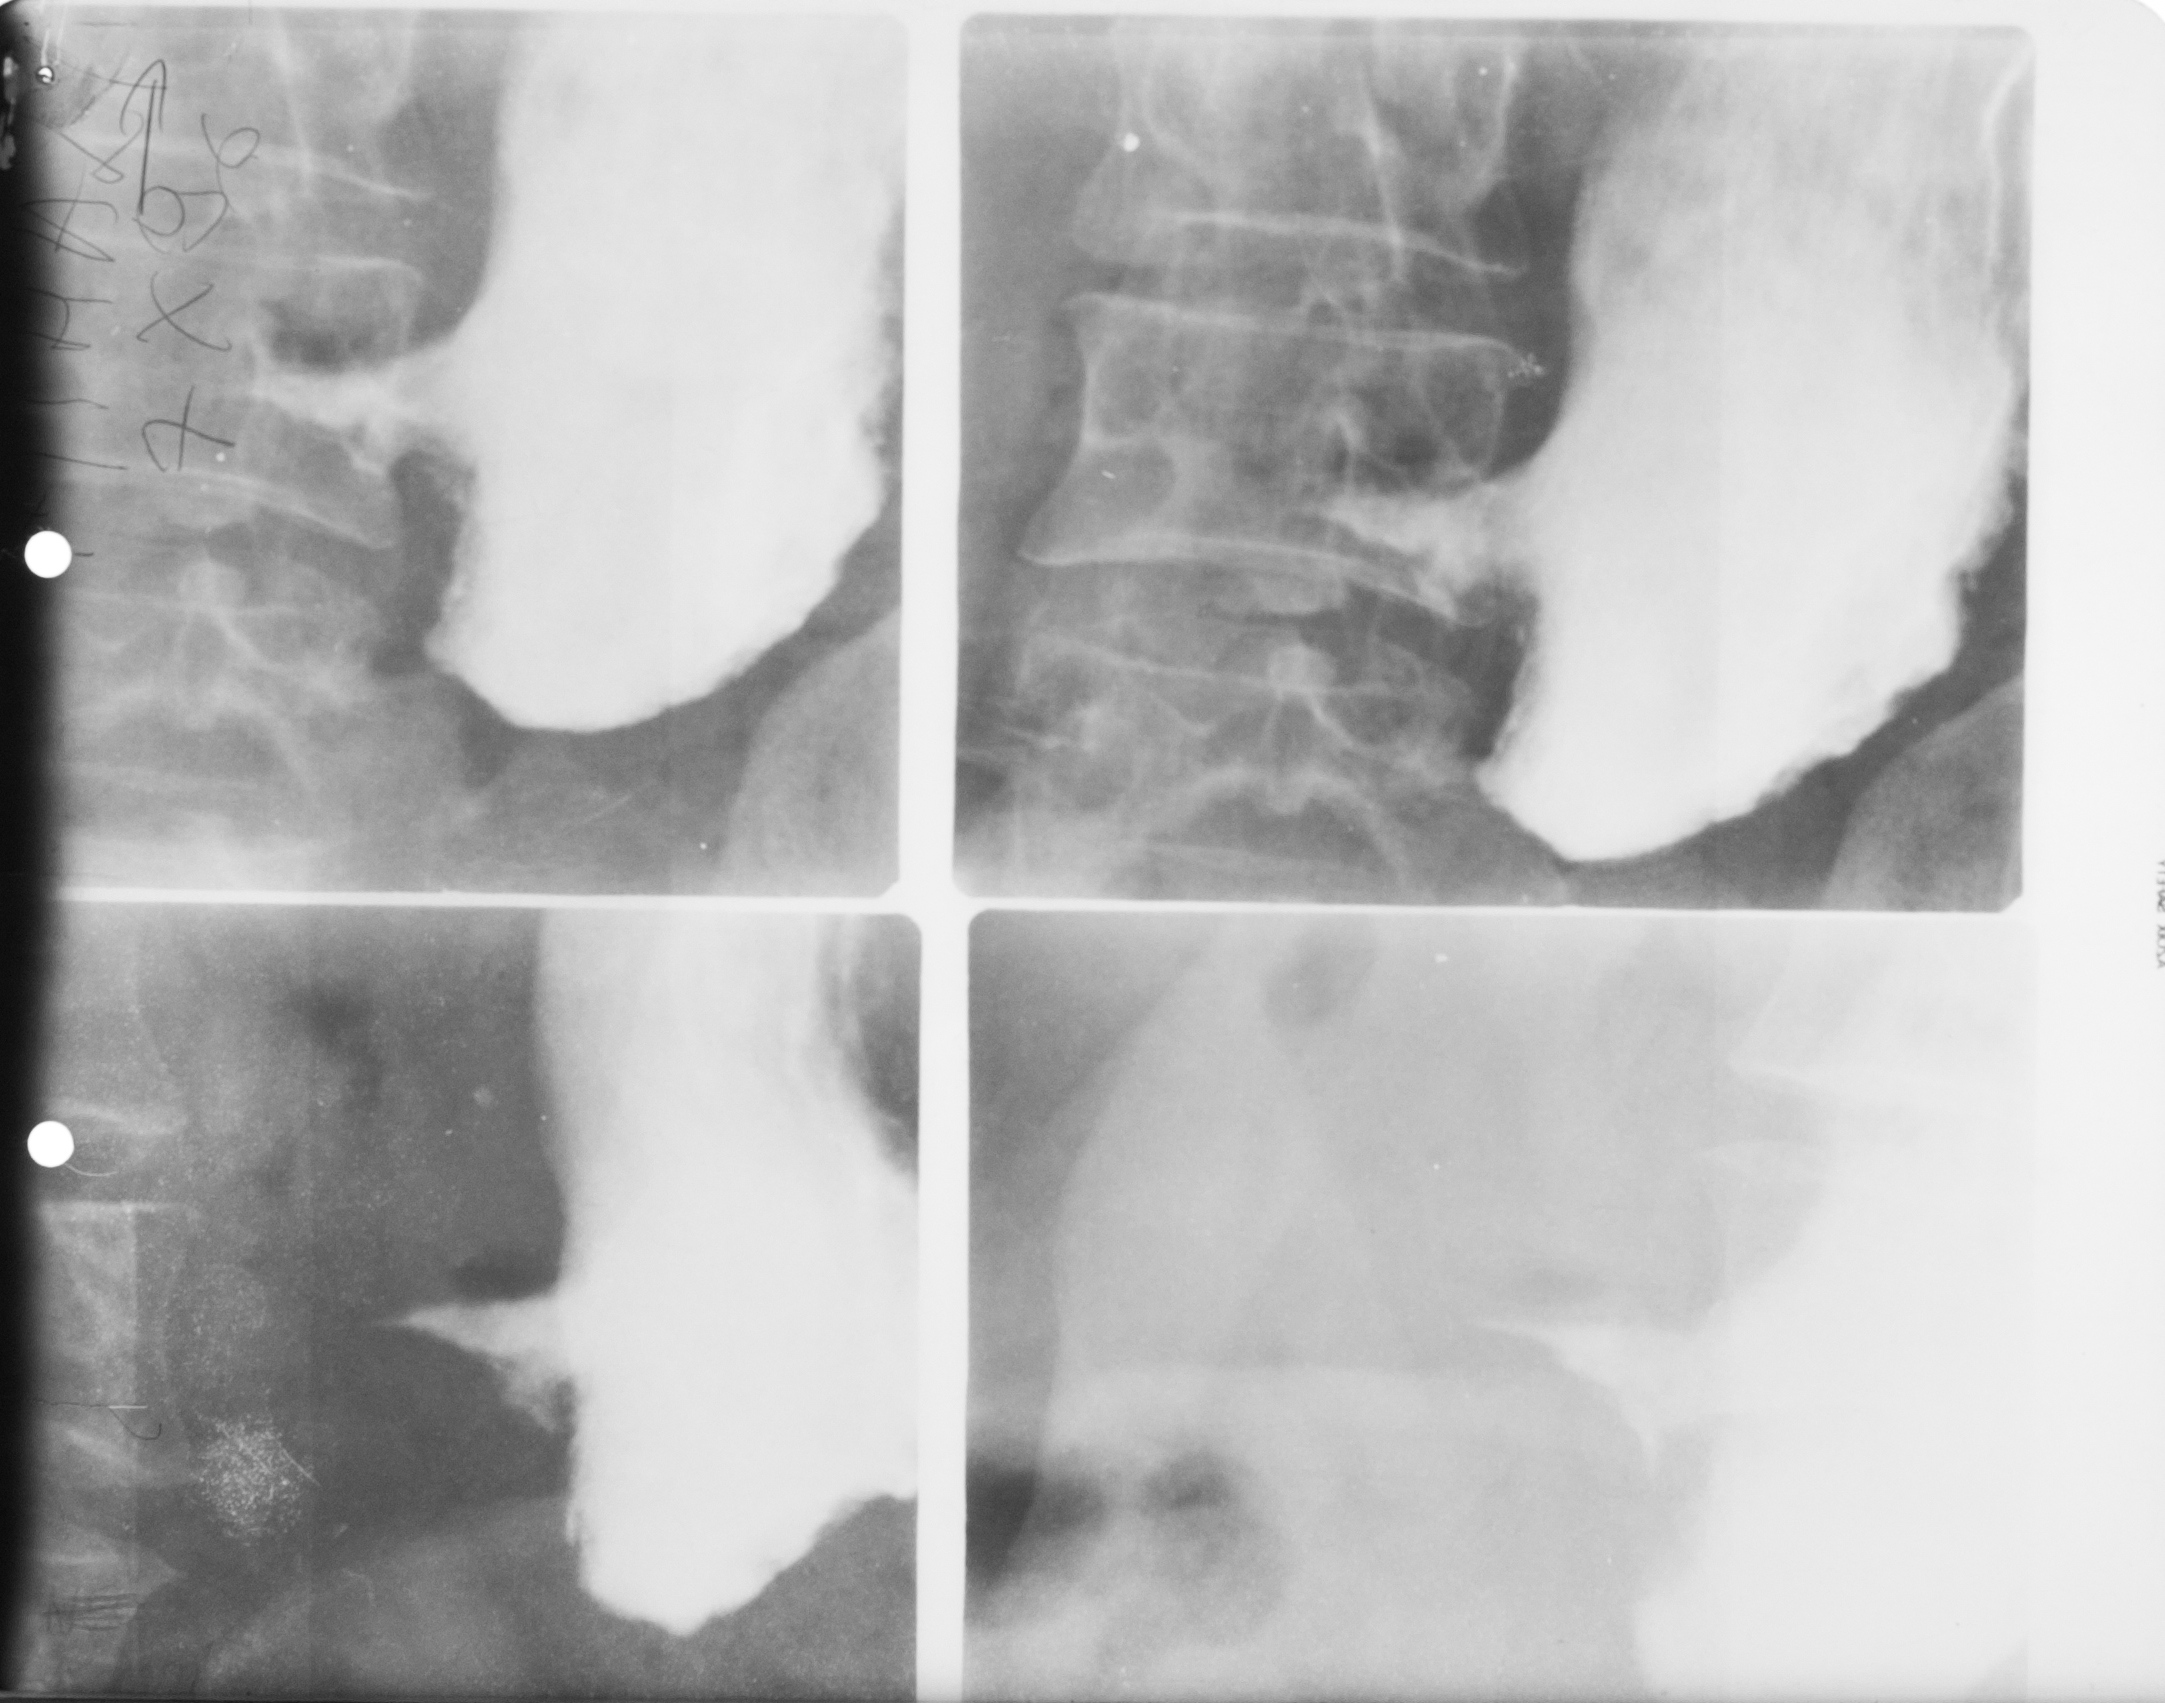

: IRIGOGRAFIE

Aspect radiologic al irigoscopiei unde recunoastem cec ascendent, flexura hepatica , transvers care este ptozat si e singura modificare care nu este neaparat patologica, flexura splenica, colon desccendent, sigmoid si rect. Absolut normal pentru persoana relativ in varsta

DEFECT DE UMPLERE (IRIGOSCOPIE/IRIGOGRAFIE)

Este rotund, bine net liniar delimitat, probabil ceva polip

DIVERTICULI (IRIGOGRAFIE)

Multiple imagini de aditie la nivelul cadrului colic

STENOZA MALIGNA = ADENOCARCINOM DE COLON

Tot irigografie cu zona de stenoza la nivelul colonului transvers, vedem coloana vertebrala si colon descendent, cu contur neregulat la extremitati, cu aspect de cotor de mar

Tot irigografie.

Zona de stenoza la nivelul colonului descendent si retrodilatatie cu aspect de pantalon de golf, proces infiltrativ la nivelul colonului. Mai putin frecvent decat adenocarcinomul

PROCES NEOPLAZIC CU STENOZĂ

Colon descendent, sigma, zona de stenoza fara mucoasa la nivelul acestei zone, proces neoplazic.

NEOPLASM

Aspect de cotor de mar cu stenoza, contur neregulat, retrodilatatii,lipsa lizereului de siguranță,deci lipsa mucoasei la acest nivel. Neoplasm